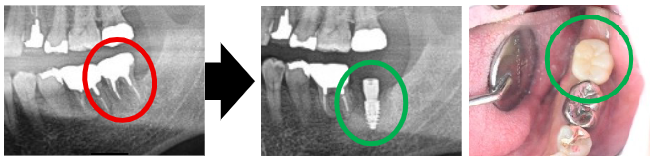

「左下の一番奥の歯の被せ物が取れそうで、動いていて、噛むと痛いです。」と来院されたのは、40代の男性、Kさんです。お口の中を拝見すると、被せ物が土台ごとグラついており、歯の根が割れていました。レントゲンで詳しく確認すると、歯の根が真っ二つに破折していて、残念ながら抜歯が必要な状態でした。Kさんから「抜いたあとは、どうなるんでしょうか?」というご質問がありました。

それぞれの治療のメリットとリスクについてご説明させていただいたところ、Kさんは『インプラント』を選ばれました。奥歯がなくなると、噛む力や食事の楽しさが大きく変わってしまいます。インプラントは他の歯を守りつつ、しっかり噛める最良の方法といえます。先日、定期健診にお越しになりましたが、インプラントはしっかり機能し、不具合なくお使いいただけていました。